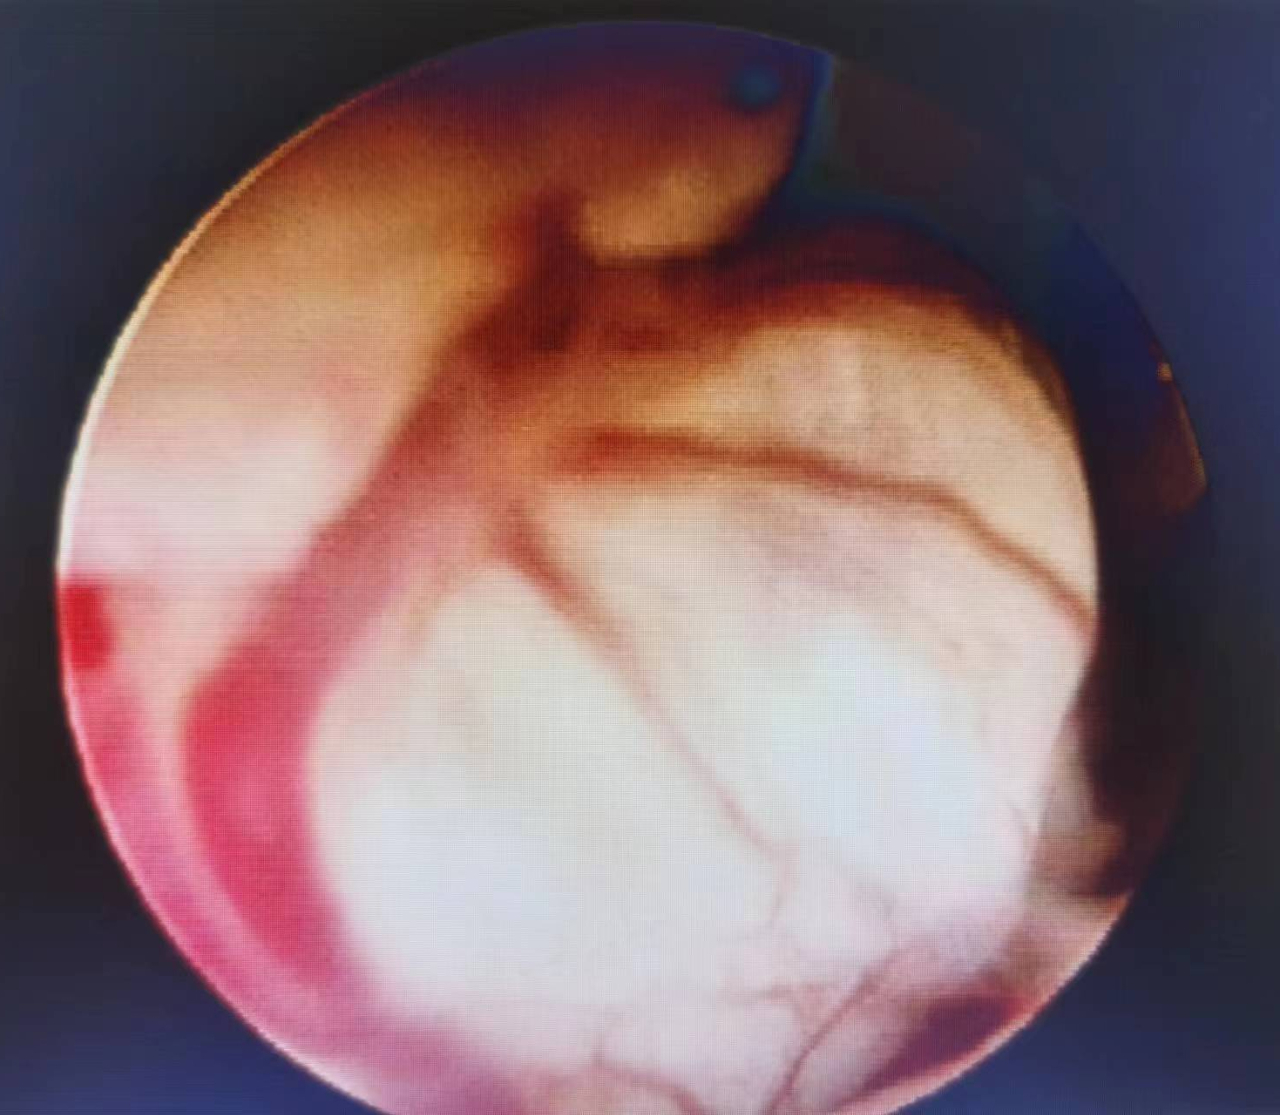

血管明显扩张扭曲